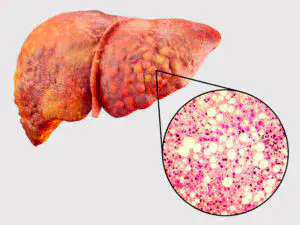

VOCÊ ESTÁ PROTEGIDO CONTRA A GORDURA NO FÍGADO?

1 em cada 4 pessoas terá um fígado gordo, doença que pode progredir para 3 diferentes estágios.

Estágio 1: Acúmulo de gordura nas células do fígado

A dieta moderna faz uso intensivo de açúcares e carboidratos, que são convertidos em gordura pelo corpo. Isso pode resultar no acúmulo de gordura nas células do fígado.

Estágio 2: Resposta Inflamatória

Esse acúmulo de gordura nas células do fígado causa uma resposta inflamatória auto-imune, na qual anticorpos são enviados para atacar o próprio órgão.

Estágio 3: Função Hepática Reduzida

A inflamação reduz a capacidade do fígado de funcionar adequadamente, impactando negativamente sua capacidade de desintoxicar o corpo e processar impurezas, causando maior acúmulo de gordura no fígado.

QUAIS SÃO AS CONSEQUÊNCIAS DA INFLAMAÇÃO

Se nada for feito, um fígado gordo pode levar à cirrose hepática, condição grave que requer grandes mudanças no estilo de vida.

A Causa Biológica de um Fígado Gordo

Os pesquisadores identificaram a "mãe de todos os antioxidantes", que protege o fígado contra a inflamação.